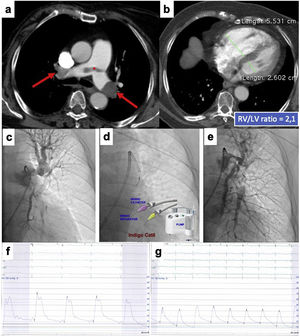

This is the case of an 86-years old woman who had a recent ischemic stroke and was admitted with an acute intermediate-high-risk PE, catheter-directed therapy proposed due to respiratory failure (paO2/FiO2 ratio=170), with no response to parenteral anticoagulation. a) and b) Axial contrast enhanced computed tomography at time of diagnosis illustrates central extensive bilateral thrombus (red arrows) and huge dilatation of right ventricle (RV/LV ratio of 2.1). c) Selective pulmonary angiography confirms obstruction of left inferior lobar artery and lingula. d) Continuous aspiration mechanical thrombectomy was performed with Indigo® CAT8. A Penumbra Indigo System Separator SEP8 device was used through the aspiration catheter to facilitate clot aspiration by preventing the catheter from clogging in the extensive thrombus. e) Post-procedure we observe a near restoration of the normal perfusion in the left lung. f) and g) There was a decrease in systolic and mean pulmonary artery pressure of 65 and 33 mmHg pre-procedure, respectively, to 42 and 25 mmHg post-procedure. PaO2/FiO2 ratio increased to 371 at 48 hours after intervention.

At the end of the percutaneous procedure, we performed a final selective pulmonary angiography and reassessed the hemodynamic parameters. Figures 2 and 3 illustrate different situations in which the technique was applied.